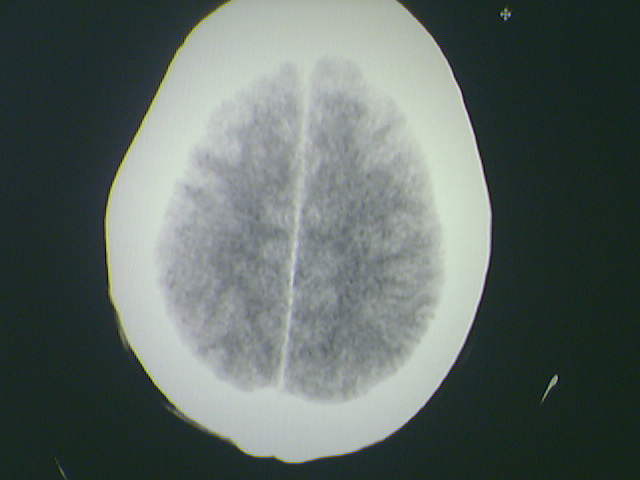

标题: CT21792:男48岁,头痛昏一月加重伴双下肢无力一天,反应迟 [打印本页]

标题: CT21792:男48岁,头痛昏一月加重伴双下肢无力一天,反应迟

水肿占位效应明显,支持脑转移瘤诊断

支持 多发性脑转移瘤。